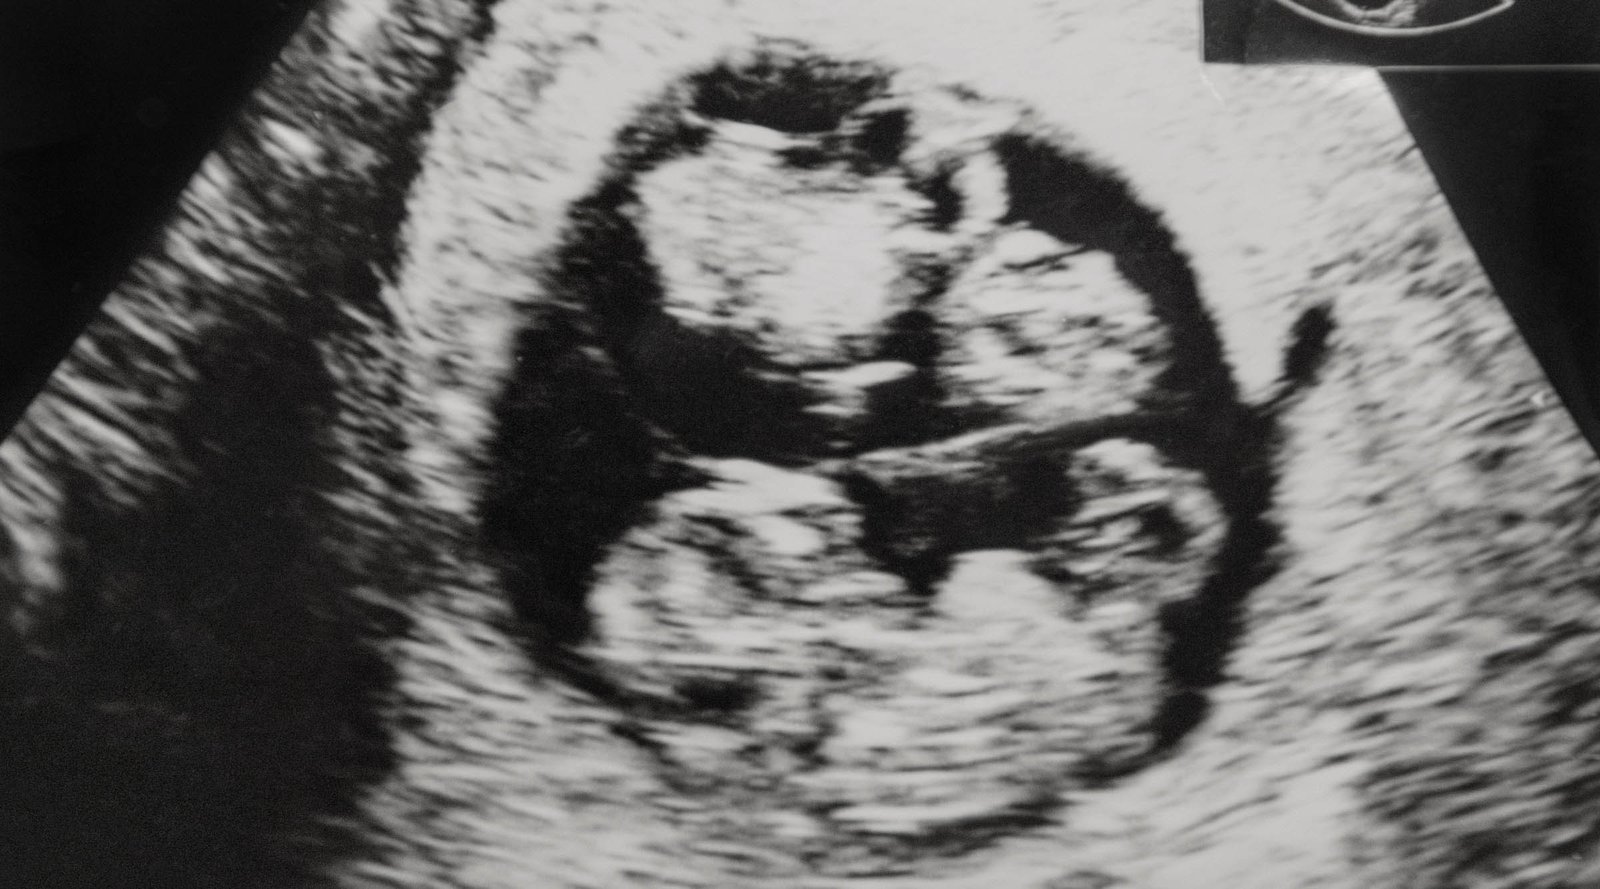

Seguir as orientações do seu obstetra, cuidar da alimentação e entender as particularidades do parto de gêmeos são passos fundamentais para uma experiência segura e tranquila. Cada ultrassom e cada consulta fortalecem a preparação para a grande chegada.

Quantos ultrassons são feitos no pré-natal de gêmeos?

Você fará mais ultrassons do que em uma gestação única. Eles são essenciais para acompanhar o crescimento individual de cada bebê, o volume de líquido amniótico e garantir que ambos estão se desenvolvendo bem.